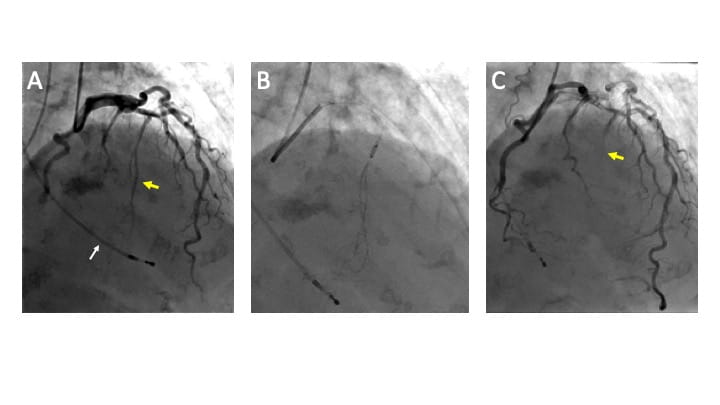

On the day of the procedure, baseline echocardiography again demonstrated severe LVOT obstruction due to septal hypertrophy. Via a right jugular approach, a temporary pacing wire was placed to provide immediate backup should complete heart block occur, and coronary angiography demonstrated the coronary anatomy. (Figure 3, panel A) Initial hemodynamics via left heart catheterization demonstrated a provoked (post-PVC) gradient of 100 mm Hg. (Figure 2) A wire was placed into the 1st septal perforator artery, and an over-the-wire balloon was inflated to isolate the larger branch of the artery. However, a test injection of a mixture of iodinated contrast mixed with microbubble contrast under simultaneous fluoroscopic and echocardiographic visualization demonstrated inadequate coverage of the hypertrophied region. The balloon was then repositioned more proximally to provide adequate coverage of the entire basal septum. (Figure 3, panel B) Echocardiography was performed specifically to rule out extension of the contrast to remote regions of the myocardium. A total of 1.8 mL of ethanol was slowly injected via the inflated over-the-wire balloon. The patient reported mild to moderate angina, which was controlled with medication. Angiograms following the injection demonstrated absent flow in the 1st septal perforator. (Figure 3, panel C)

Figure 3. A – Coronary angiogram demonstrating the target 1st septal perforator artery (yellow arrow), and temporary pacing wire in the right ventricle (white arrow). B – Occlusion of the proximal 1st septal perforator artery with an over-the-wire balloon and injection of contrast into the perforator artery. C – Demonstration of lack of flow down the target septal perforator artery (yellow arrow).